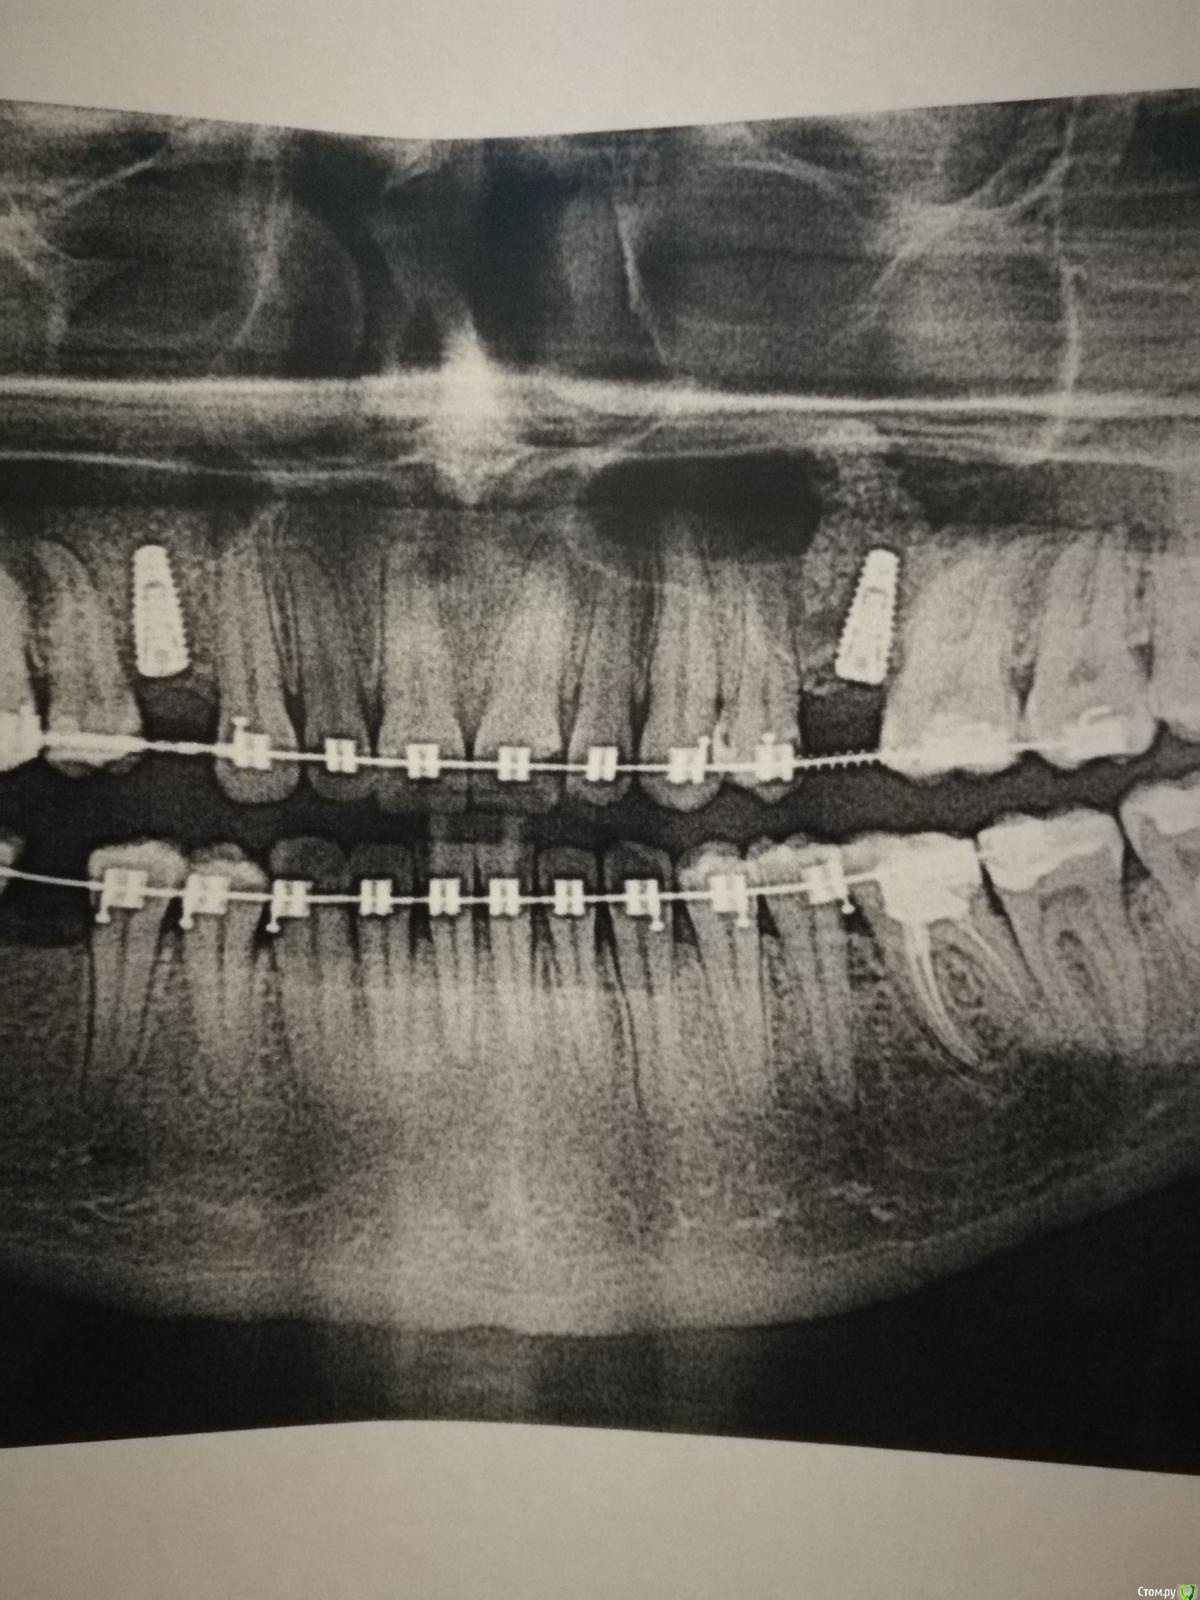

Nadin1 Опубликовано 23 декабря, 2018 Поделиться Опубликовано 23 декабря, 2018 (изменено) Здравствуйте! Нужна ваша консультация. 17 декабря был сделан открытый синус лифтинг и одномоментно установлено 2 импланта. Меня беспокоит не слишком ли близко к корню зуба установлен имплант? Мой хирург говорит, что нормально. Снимки прикрепляю. Спасибо. Изменено 23 декабря, 2018 пользователем Nadin1 Ссылка на комментарий